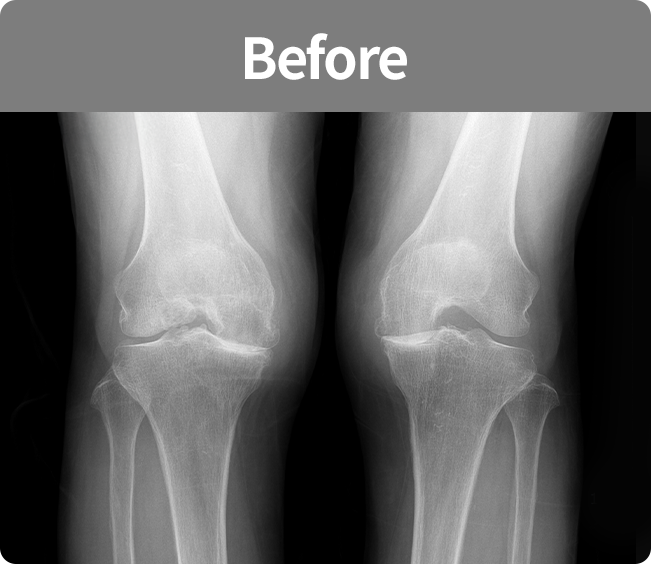

인공 관절 치환술

퇴행성관절염 및 기타 관절손상으로 통증이 심해

정상생활을 할 수 없고 다른 치료나 시술로

효과가 없는 경우에 시행하는 수술법

(부분 치환술, 전 치환술)

정상생활을 할 수 없고 다른 치료나 시술로 효과가 없는 경우에 시행하는 수술법(부분 치환술, 전 치환술)